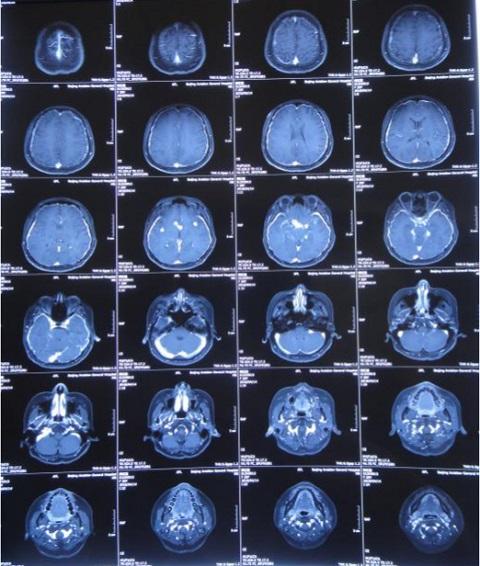

8月16日,患者脑脊液仍然色黄浑浊,复查增强MRI现实四叠体池区、鞍区、环池内多发结核脓肿。

10月18日,患者脑脊液外观基本清亮,增强头MRI现实仍然课件鞍区多发结核脓肿、四叠体池、环池内病变明显改善。

10月20日,行分流手术,术后复查增强头MRI见图。